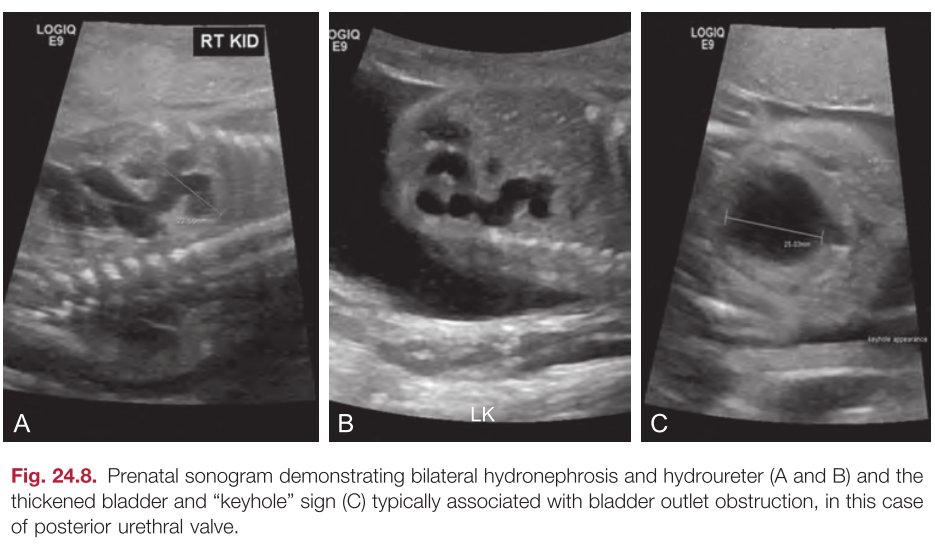

In the setting of bilateral hydroureteronephrosis, a thickened bladder, and poor emptying, voiding cystourethrography (VCUG) should be performed to rule out a _____

posterior urethral valve

UTZ FINDING of a thickened bladder and dilated posterior urethra known as the ___

KEYHOLE SIGN